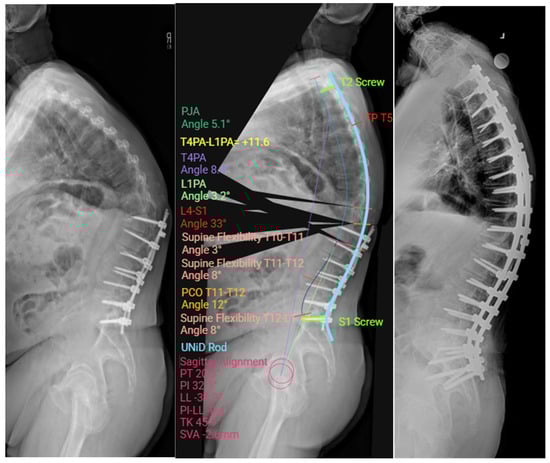

2.7. Custom Patient-Specific Rods